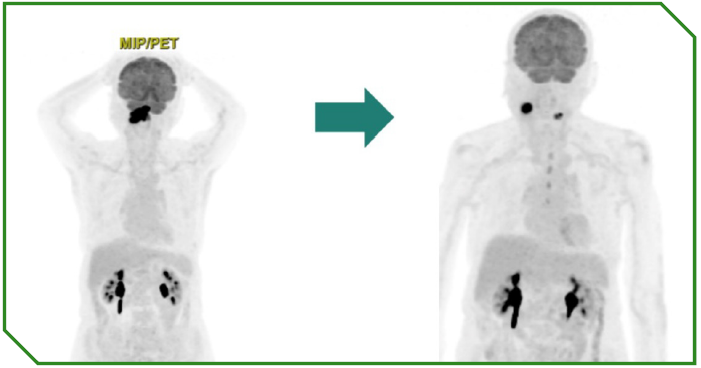

Paciente feminina de 96 anos, funcionalmente independente, diagnosticada com carcinoma espinocelular de cavidade oral localmente avançado e irresecável, com alta expressão de PD‑L1 (CPS 70). Não apresentava condições clínicas para abordagem com quimioterapia sistêmica. Considerando idade avançada, contexto funcional e perfil molecular tumoral, foi instituída imunoterapia isolada como tratamento de primeira linha.